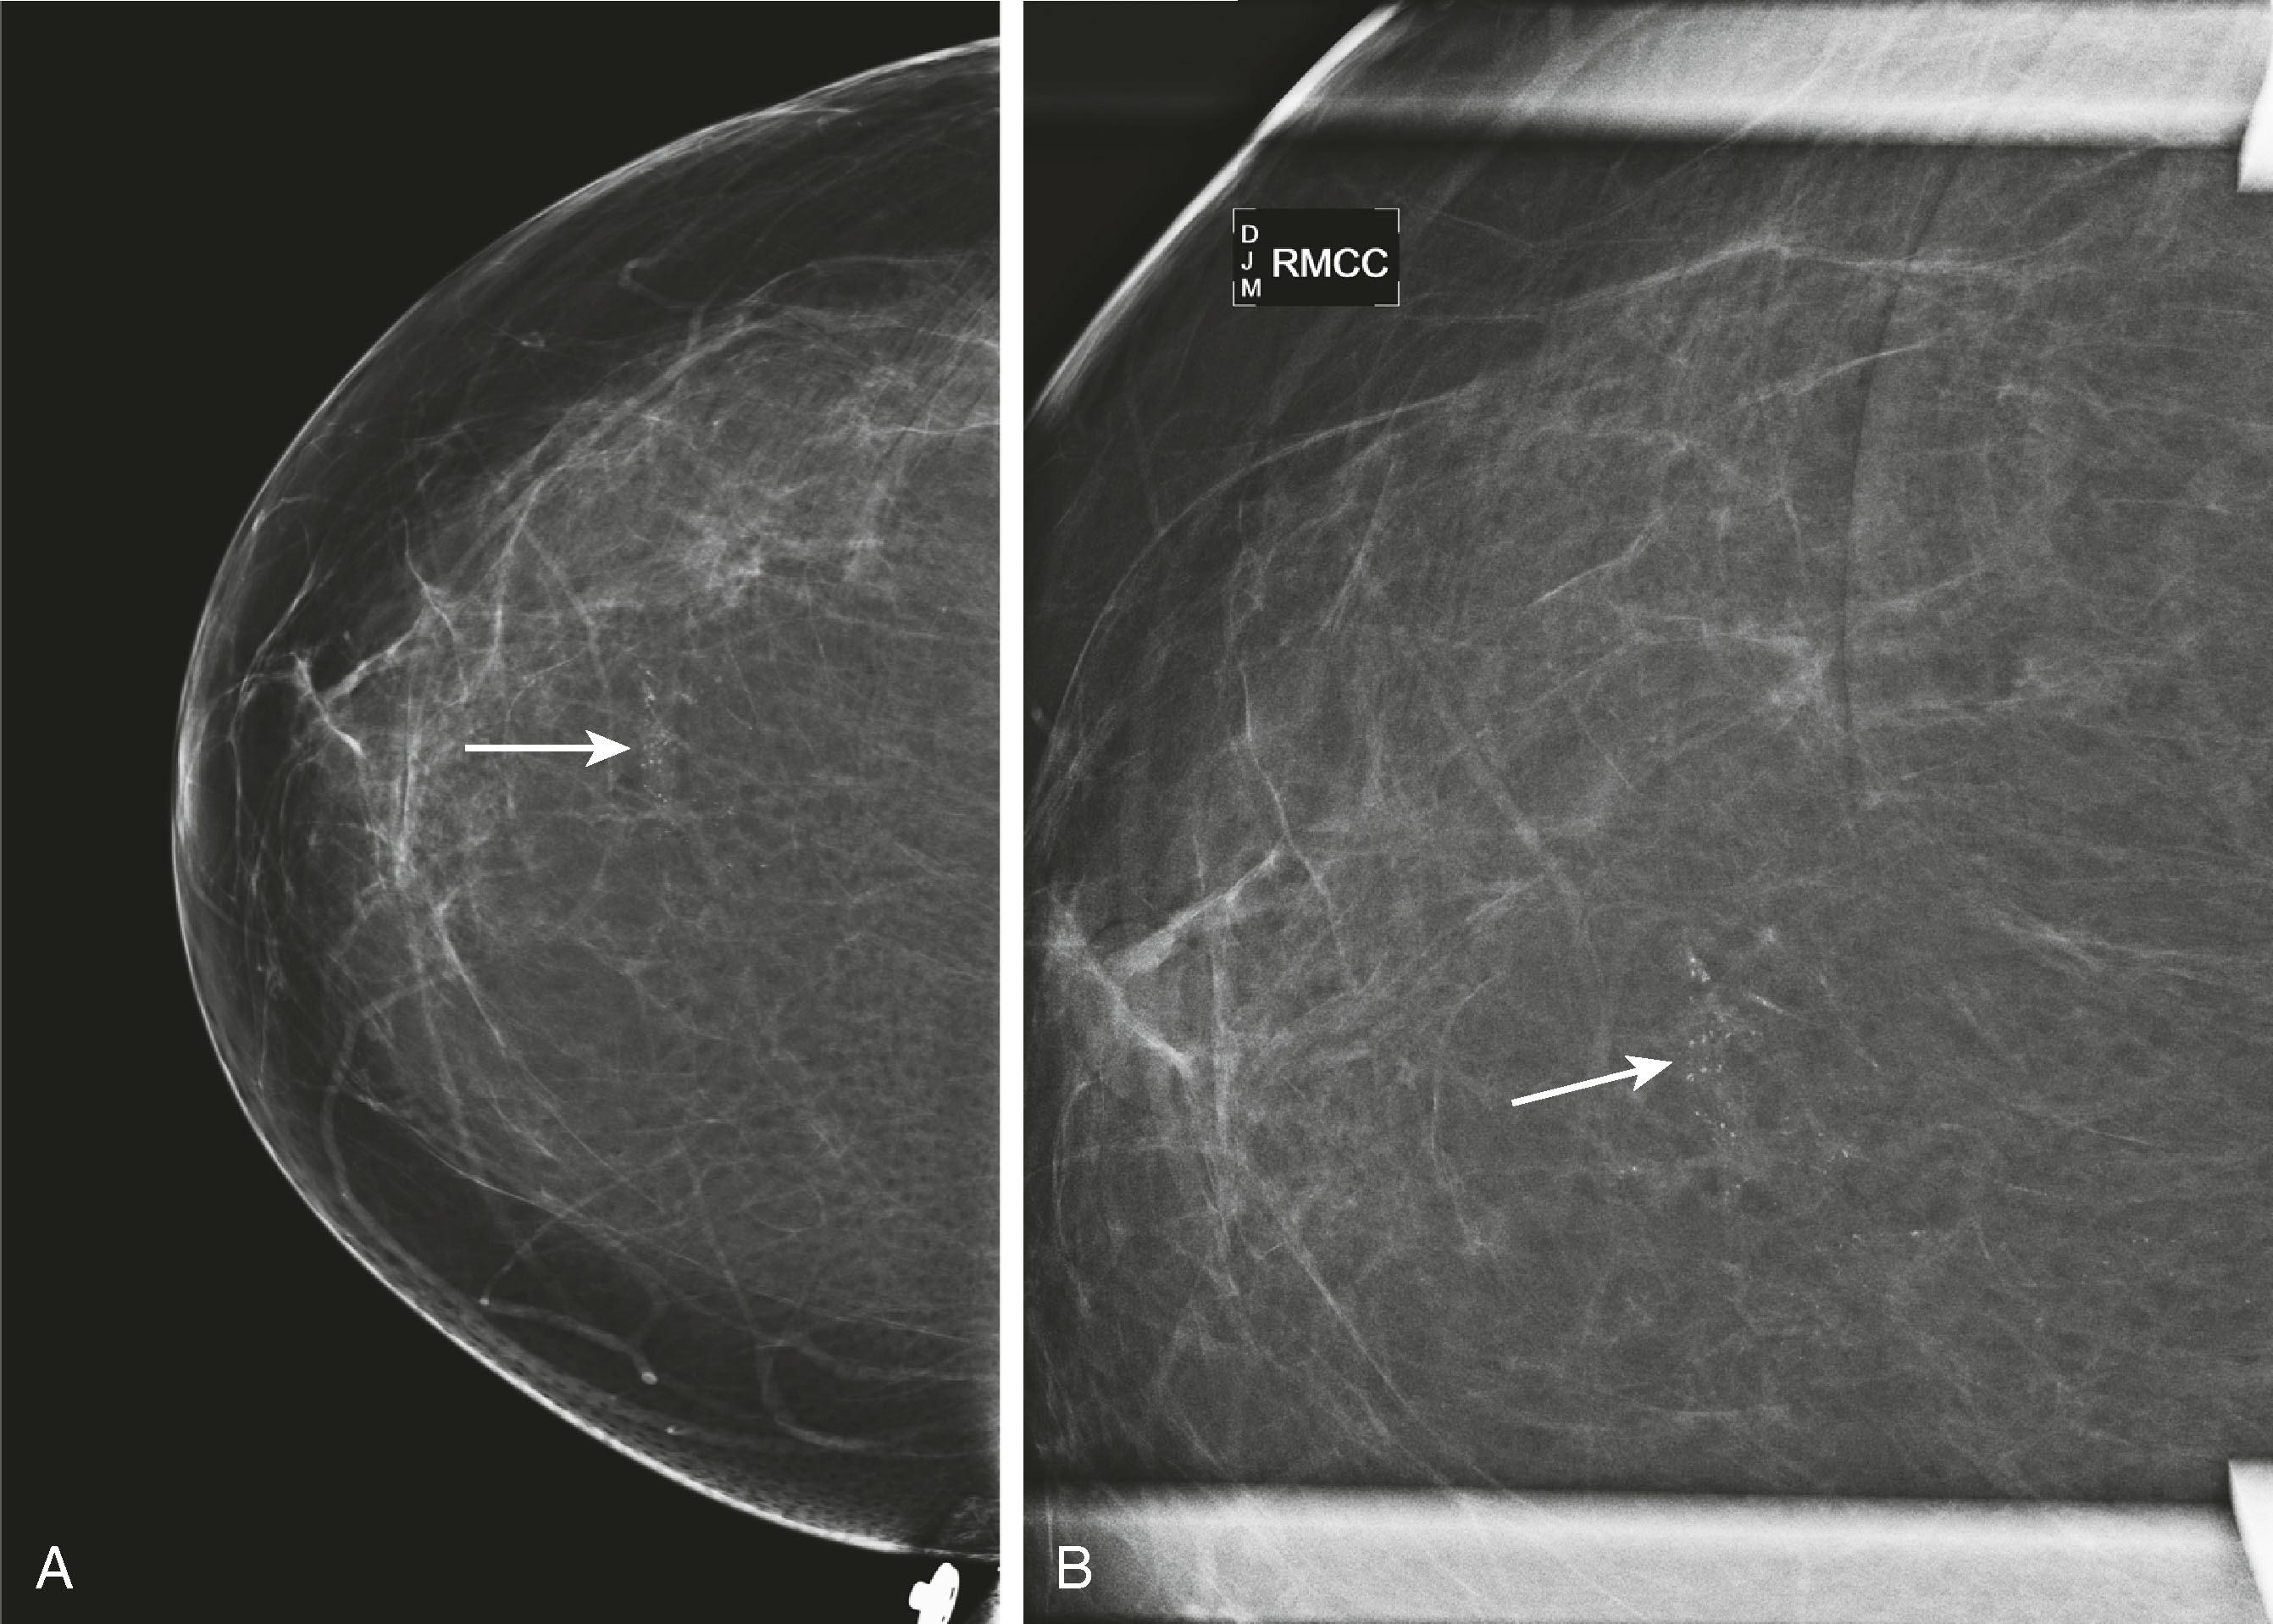

Breast MRI has become the gold-standard test to search for a breast primary when a patient presents with a carcinoma of unknown primary. It is valuable not only because of its high sensitivity in identifying the primary tumor but also because of its high negative predictive value. Liberman and associates noted in a small study group of 16 women that MRI identified the primary breast tumor in 13 out of 16 patients. MRI may be of greatest value when a patient presents with axillary lymphadenopathy and a negative mammogram. Fig. 8.35 demonstrates such a patient who presented with axillary lymphadenopathy and a negative mammogram.

Fig. 8.35, A 42-year-old woman was noted to have prominent right axillary lymph nodes and had excisional biopsy of one of the lymph nodes, which revealed carcinoma. Her mammogram did not reveal the primary carcinoma. ( A ) Abnormal mammogram of the right breast. ( B ) Right axillary ultrasound demonstrates enlarged lymph nodes (arrow) . ( C ) Magnetic resonance imaging (MRI) demonstrates the right axillary adenopathy (arrow) . ( D ) MRI additionally demonstrates the occult primary breast malignancy (arrow) .